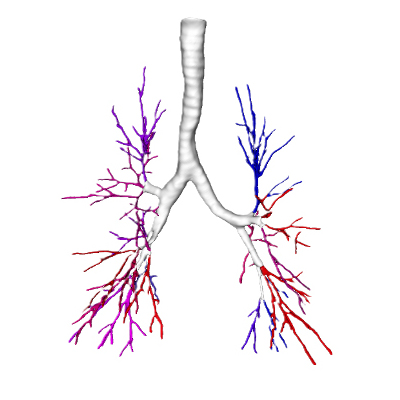

Bronchial tree

Anatomical segmentation

Pulmonary arteries & veins

Advanced airway segmentation for navigational bronchoscopy planning

Recent studies demonstrate that LungQ®’s airway segmentation now matches and potentially surpasses expert-level manual assessment for bronchoscopy planning. By achieving subcentimeter alignment with expert-marked routes alongside fewer missed bifurcations, the AI tool provides a level of planning accuracy previously only mastered by experienced clinicians.

This evidence marks a major milestone in navigational bronchoscopy. By standardizing high-quality planning, LungQ® has the potential to broaden access to advanced navigational bronchoscopy, empowering clinical settings everywhere to deliver expert-level results at scale independent of local experience.